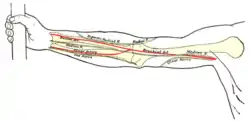

Click image to enlarge - ulnar nerve is visible in lower left | |

The right brachial plexus (infraclavicular portion) in the axillary fossa; viewed from below and in front. Front of right upper extremity, showing surface markings for bones, arteries, and nerves.

Front of right upper extremity, showing surface markings for bones, arteries, and nerves. Back of right upper extremity, showing surface markings for bones and nerves.